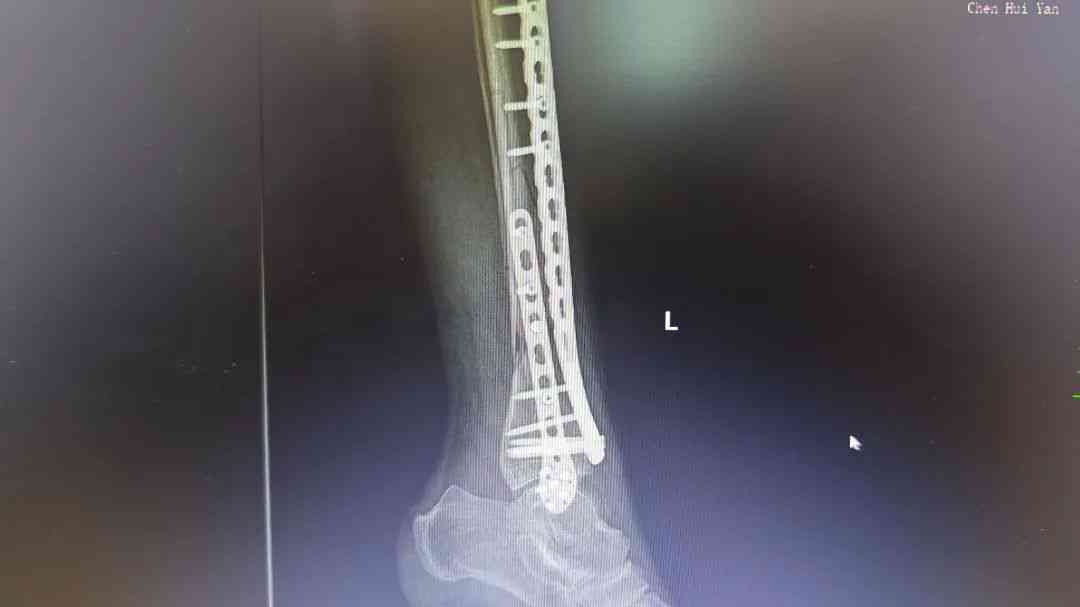

微信图片_20250512172734.jpg 微信图片_20250512172737.jpg

术后腿部影像

胸外科专家会诊后确认,患者肋骨骨折无明显位移,决定采用胸带固定配合卧床静养的保守治疗方案。针对更为复杂的小腿骨折,骨科团队在5月4日由张均锦主刀,曹桂青、陆仕邦医师协助下实施了精准复位手术。术中使用接骨板进行内固定后,X光显示骨折端对位良好,术后第三天患者已能进行简单的足部活动。